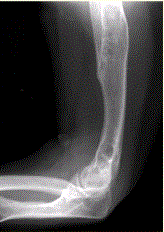

问题 患者男,22岁,长期存在骨和关节变形,近期出现右肘关节疼痛,进行性加重。行右肘关节X线正侧位片检查,见下图。 病变显示的征象包括

选项 A.累及干骺、骨干 B.累及多骨 C.髓腔内混杂密度影,病灶内含钙化 D.骨破坏形成软组织肿块 E.出现骨变形 F.受累骨未见骨膜反应

答案 ABCEF